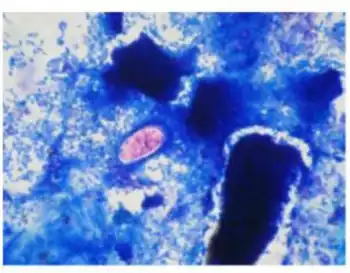

| strained oocyst of Cystoisospora belli | |

A fully mature (sporulated) oocyst of genus Isospora is a spindle-shaped body that has two sporocysts that contain four sporozoites each.[4]

The oocysts of Cystoisospora belli are long and oval shaped. They measure between 20 and 33 micrometers in length and between 10 and 19 micrometers wide.[5]

Cystoisospora belli is diagnosed by identification of the oocyst through examining a stool sample under a microscope. The diagnostic stage is the immature oocyst that contains a spherical mass of protoplasm. In other words, the oocyst that is diagnosed in the stool sample is unsporulated, and contains only one sporoblast.[2] For stool diagnosis, direct smear, concentration smear, microscopic wet mount, or iodine stains of fecal smears are adequate. But for easy screening, acid-fast stains is recommended.[2][3] If stool test is negative, and biopsies of the small intestine is performed, different stages of schizogony and sporogony should exist in the epithelial cells, but the alteration of the villi is not necessarily present.[2]